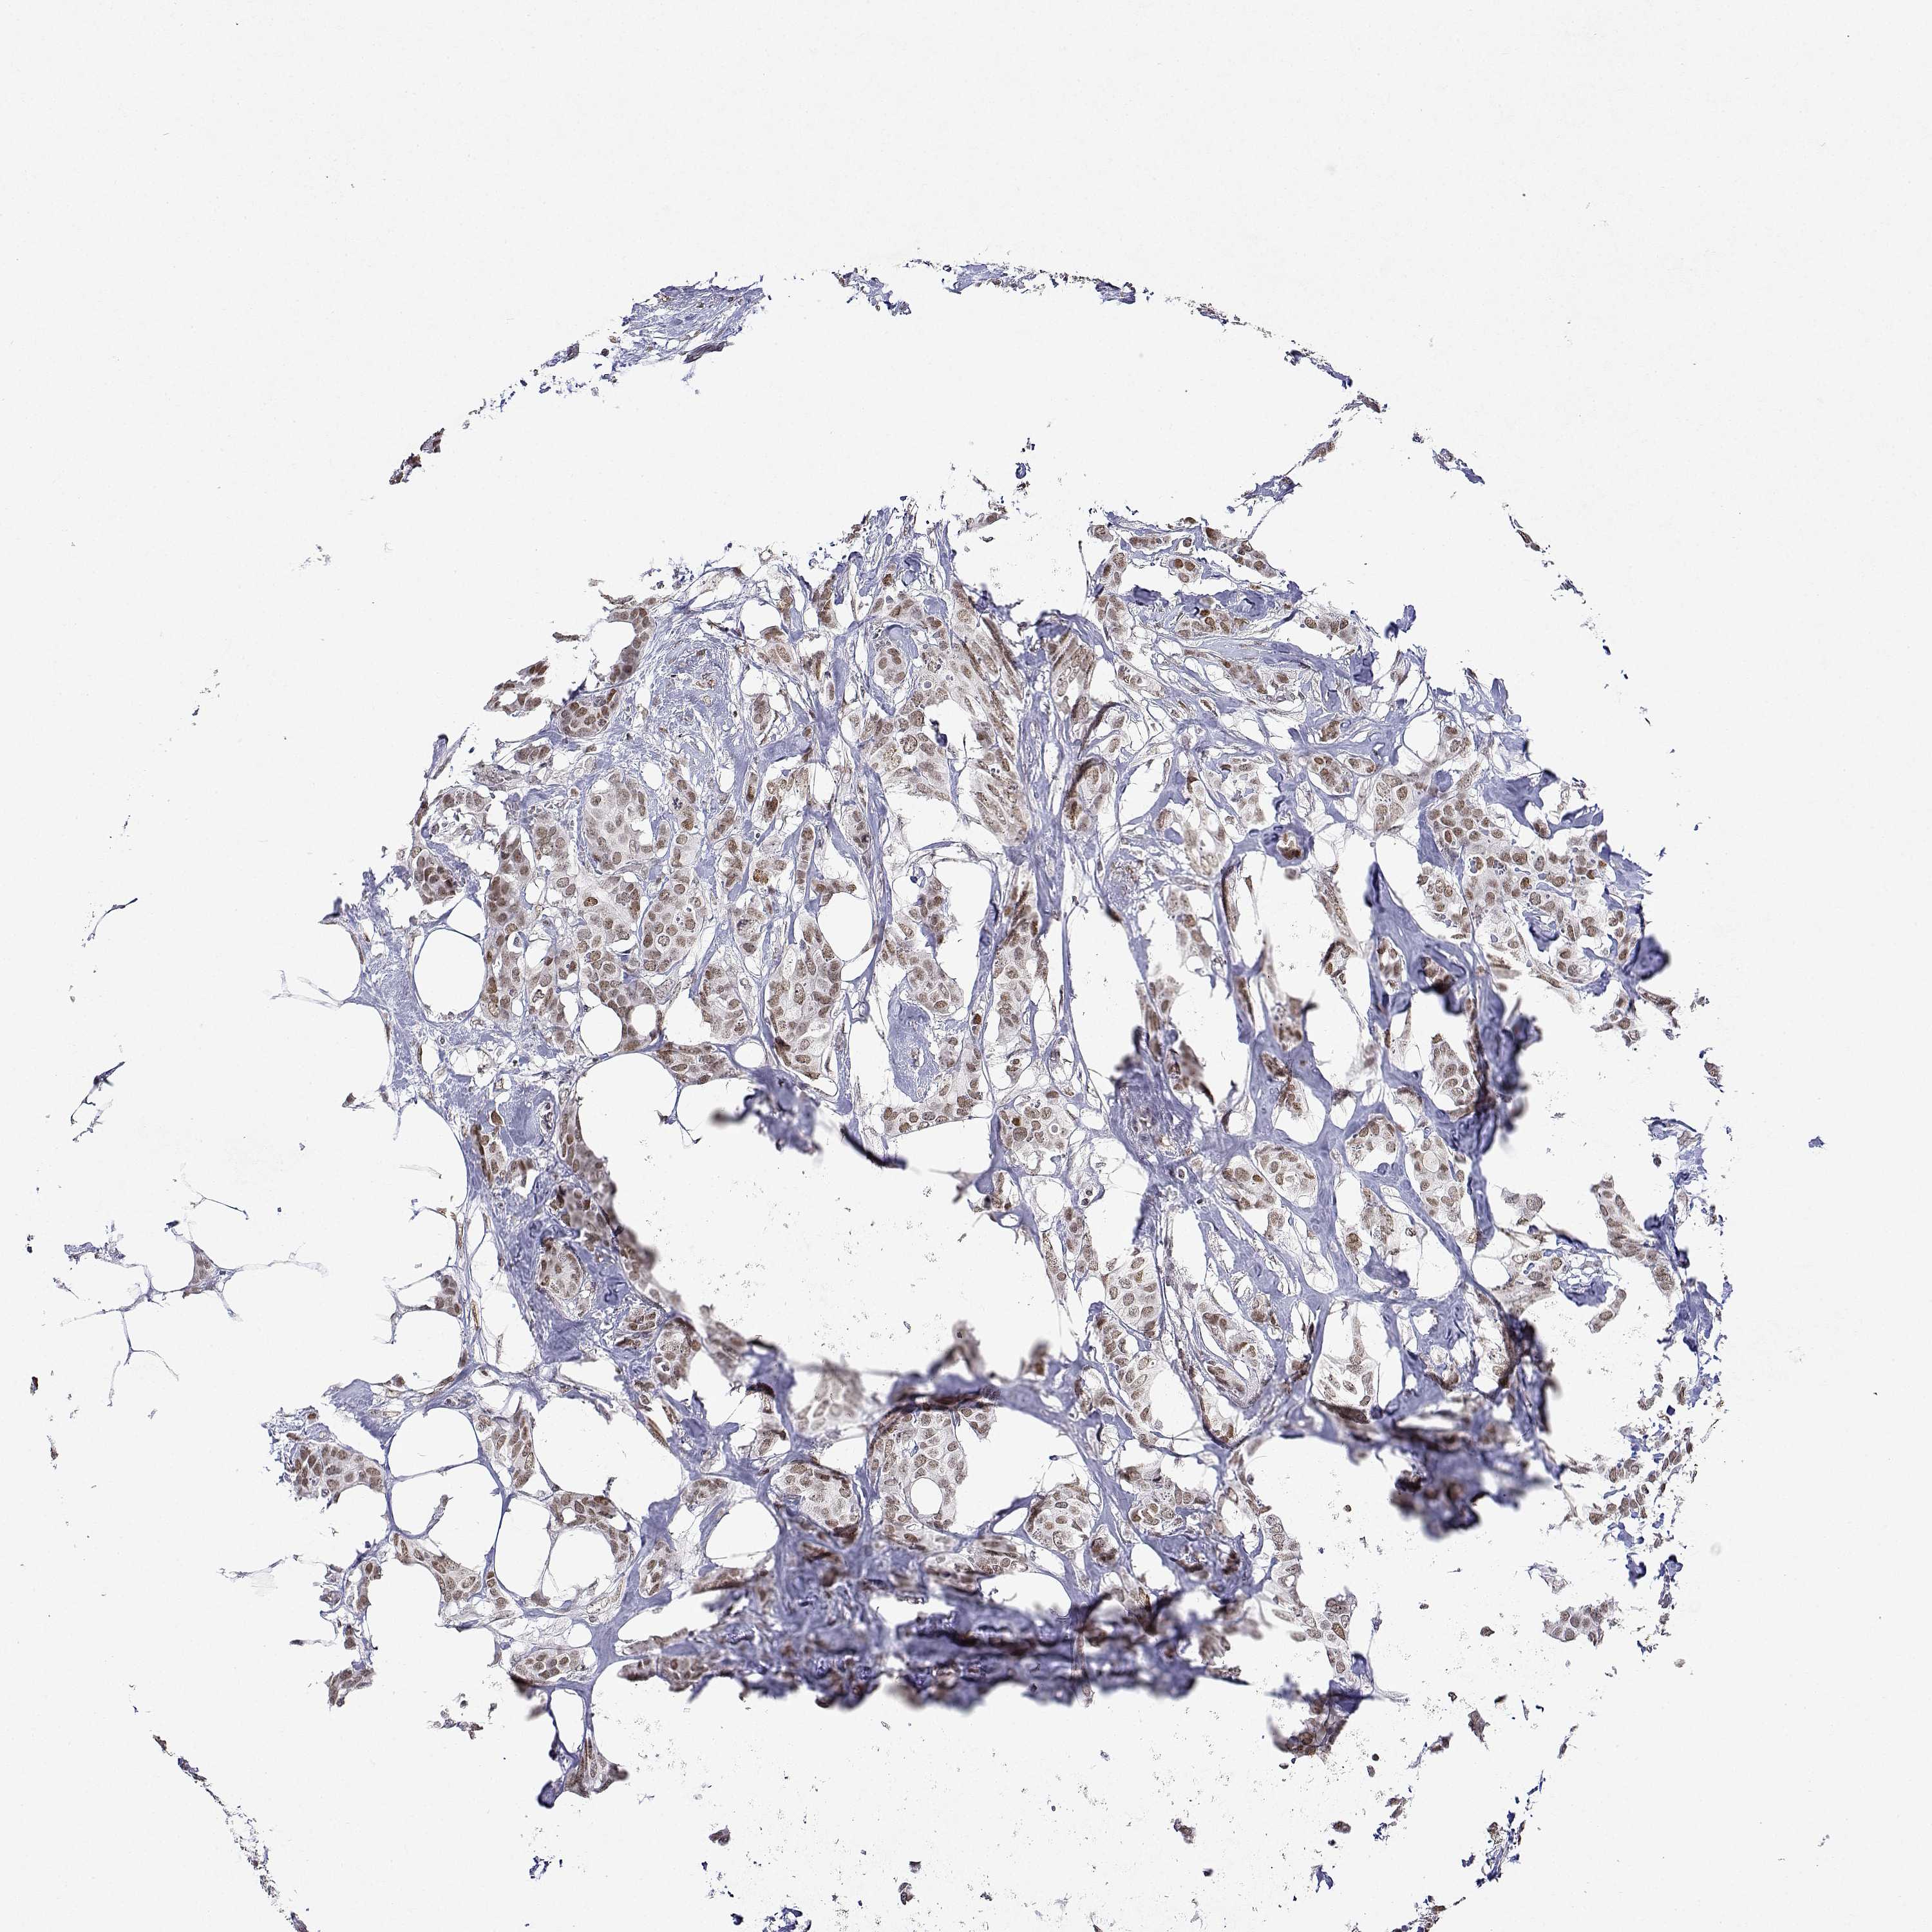

CANCER BREAST CANCER Show tissue menu

Breast cancer

Human cancer